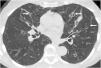

La patología de las vías respiratorias de medio calibre (bronquios segmentarios y subsegmentarios) es común y se presenta con síntomas respiratorios poco específicos, como tos, infecciones de repetición y en ocasiones hemoptisis. La dilatación permanente del árbol bronquial se conoce como «bronquiectasia» y representa un reto diagnóstico. El análisis de la distribución regional de las bronquiectasias en los diferentes lóbulos pulmonares es la guía diagnóstica más útil. El objetivo de este trabajo es describir los hallazgos de imagen de las bronquiectasias y sus diferentes tipos, revisar las situaciones más comunes y proponer un algoritmo diagnóstico basado en su distribución anatómica. Las bronquiectasias son un hallazgo frecuente, resultado de un amplio espectro de enfermedades. Los estudios de imagen desempeñan un papel esencial en su detección, clasificación y orientación diagnóstica hacia la patología subyacente

Diseases that involve the medium caliber airways (segmental and subsegmental bronchi) are common and present clinically with nonspecific respiratory symptoms such as cough, recurrent respiratory infections and occasionally, hemoptysis. The abnormal and irreversible dilation of bronchi is known as “bronchiectasis”. The diagnosis can be challenging and the analysis of the regional distribution of the bronchiectasis is the most useful diagnostic guide. The objective of this manuscript is to describe the main imaging findings of bronchiectasis and their classification, review the diseases that most commonly present with this abnormality, and provide an approach to the diagnosis based on their imaging appearance and anatomic distribution. Bronchiectasis is a frequent finding that may result from a broad range of disorders. Imaging plays a paramount role in diagnosis, both in the detection and classification, and in the diagnosis of the underlying pathology.